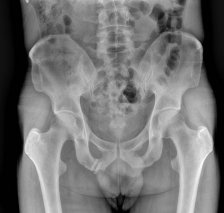

¹æ»ç¼± °Ë»ç :  ÁÂÃø °í°üÀý  ¿ÜÃø ¿Í¼ø°ú °üÀý³¶ºÎÀ§  ¼®È¸È­(+)(»çÁø10) * »çÁøÀ» Ŭ¸¯Çϸé ÇØ´ç »çÁøÀÌ º¸ÀÔ´Ï´Ù.